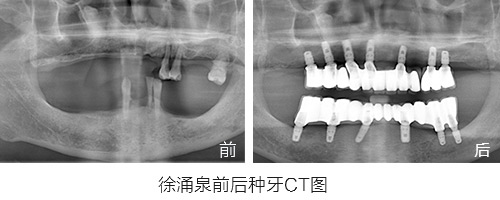

原苏州市第十七中英语老师,因为牙周炎30多岁就开始缺牙,陆陆续续共佩戴更换了5副假牙,期间多次调整,假牙带来的疼痛和牙龈发炎数不胜数。

缺牙带来最惨痛的经历:因为佩戴假牙讲课和发音十分困难,最后无奈放弃了教师职业而转岗。

种植情况:全口种植,即拔即种,植骨

种牙时间:2015年3月(已种牙1年5个月)

种植情况:全口种植

徐先生的种牙笔记:记录一年多的种牙经历